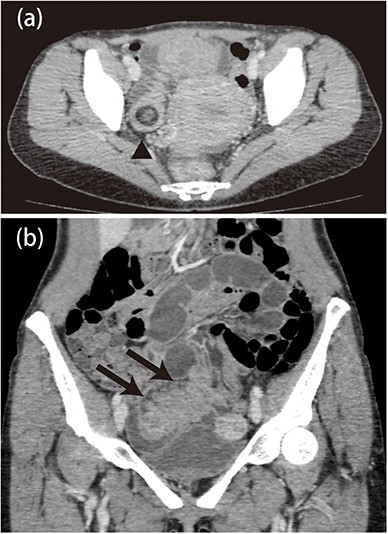

Abdominal contrast CT scan showed edematous thickening of the distal ileum (Fig. 1a), and we observed intussusception developing from a tumor lesion, with fat in the same site (Fig. 1b). Mild dilation was observed in the upper gastrointestinal tract, and there were no obvious regions of poor contrast. Based on these findings, the patient was diagnosed with intussusception of the ileum. As there were no findings suggesting gastrointestinal obstruction or impeded blood flow in the intestinal tract, the patient was scheduled for naval single-incision laparoscopically-assisted partial ileectomy.

a: Abdominal computed tomography image showing an edematous and thickened ileum with advanced intussusception of the fat tissue. b: There was mild dilatation of the proximal side of the ileum, but no ischemic changes in the intestines.